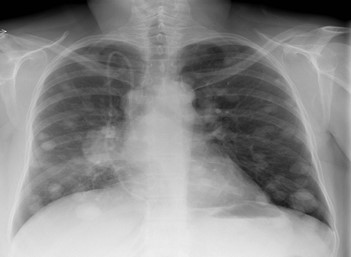

Hình ảnh di căn phổi

Nguồn: https://radiopaedia.org/articles/pulmonary-metastases